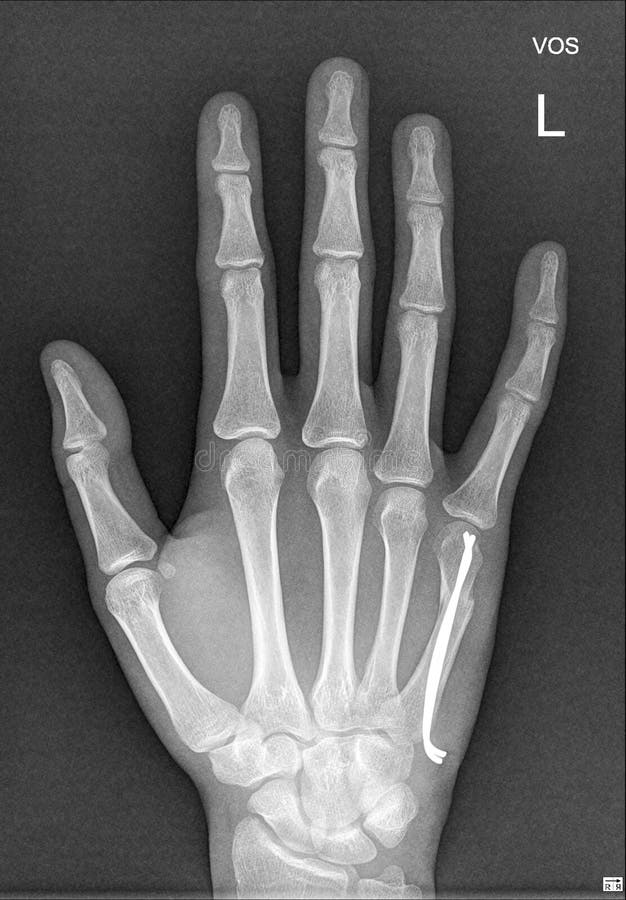

From musculoskeletalkey.com

Acute Wrist and Hand Injuries Musculoskeletal Key Small Hand Medical Condition brachydactyly is a congenital condition that a person is born with. symbrachydactyly is a congenital abnormality, characterized by limb anomalies consisting of brachydactyly,. It leads to someone’s fingers and toes being much. brachydactyly is a shortening of the fingers and toes due to unusually short bones. brachydactyly is typically a condition that affects the appearance of. Small Hand Medical Condition.